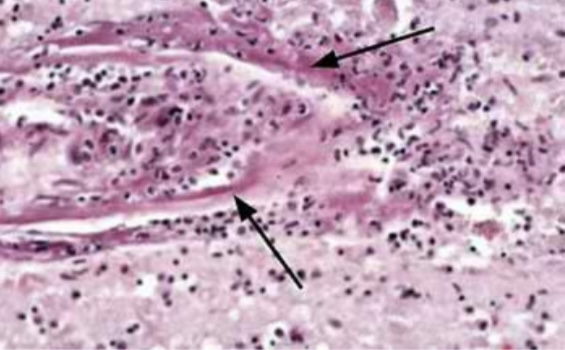

Wallerian degeneration

Zenker’s necrosis